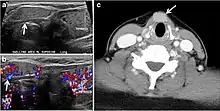

Inflammatory thyroid disorders include acute infectious thyroiditis, Hashimoto's thyroiditis, Riedel's thyroiditis, and granulomatous thyroiditis (de Quervain's). Hashimoto's thyroiditis is associated with an increased risk of lymphoma and papillary thyroid carcinoma. The CT scan findings of thyroiditis are nonspecific and variable (Figs. 14, 1515 and and16)16). The thyroid gland has a very high iodine concentration, resulting in high CT attenuation (80–100 Hounsfield Units). The presence of thyroiditis can be suggested by a diffusely enlarged and hypo-attenuating (around 45 Hounsfield Units) thyroid gland. This is probably due to follicular cell destruction and reduced thyroid iodine concentration. Marked homogeneous enhancement is typically expected. Therefore, moderate thyroid enhancement in a case of thyroiditis suggests a diffuse inflammatory process. It is essential to clinically correlate this with a thyroid function test and serum autoantibody levels.[1]

Fig. 16. Midline ectopic thyroid with Hashimoto's thyroiditis in a 49-year-old female patient. a Transverse greyscale ultrasound shows a 1.6 × 0.8 cm solid, well-defined, heterogeneous area (white arrow) in the midline, superior to the thyroid gland. It is iso-echogenic to the thyroid gland with no definite connection to the thyroid gland. b Transverse colour Doppler ultrasound shows significant increase in vascularity. c Axial enhanced neck CT scan at the level of thyroid cartilage demonstrates midline infrahyoid hyperdense soft tissue mass (white arrow) embedded within the strap muscle.[1]